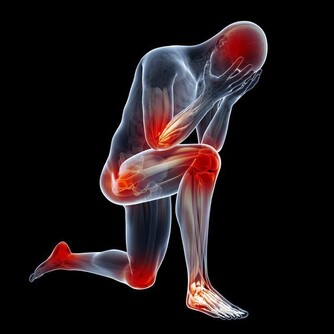

肝硬化是什麼?顧名思義,就是肝臟變硬了。正常的肝臟和嘴唇一樣柔軟有彈性,

而硬化的肝摸上去就如同鼻尖一樣,有韌性沒彈性,而且病程越長,肝臟就越硬。

疲倦乏力

疲倦乏力程度自輕度疲倦感覺至嚴重乏力,與肝病的活動程度一致,產生乏力的主要原因有三:

1. 進食的熱量不足;碳水化合物、蛋白質、脂肪等的中間代謝障礙,致能量產生不足;

2. 肝臟損害或膽汁排泄不暢時,血中膽鹼酯酶減少,影響神經、肌肉的正常生理功能;

3. 乳酸轉化為肝醣原的過程發生障礙,肌肉活動後,乳酸蓄積過多。